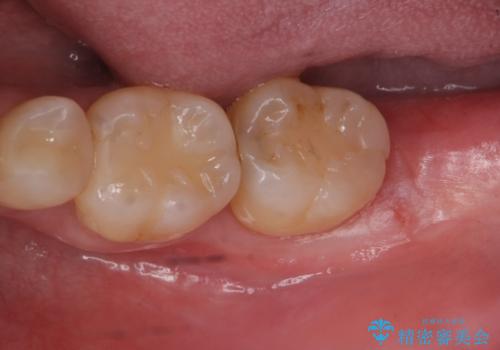

親知らず抜歯

- 親知らずを抜きたいとのことで来院。

パノラマ写真(二次元的な写真)だと、下歯槽神経が近いかどうかわからないので

CT(三次元)を撮り、神経が近くないことを確認して抜歯を行いました。

親知らずがあると手前の歯との隙間に汚れが溜まりやすく、歯ブラシで磨く事はできないため、虫歯になりやすいです。

親知らずは虫歯になれば抜歯をすればいいのですが、手前の歯が虫歯になったら治療が必要になります。

ですので虫歯になる前に抜歯をすることをおすすめします。